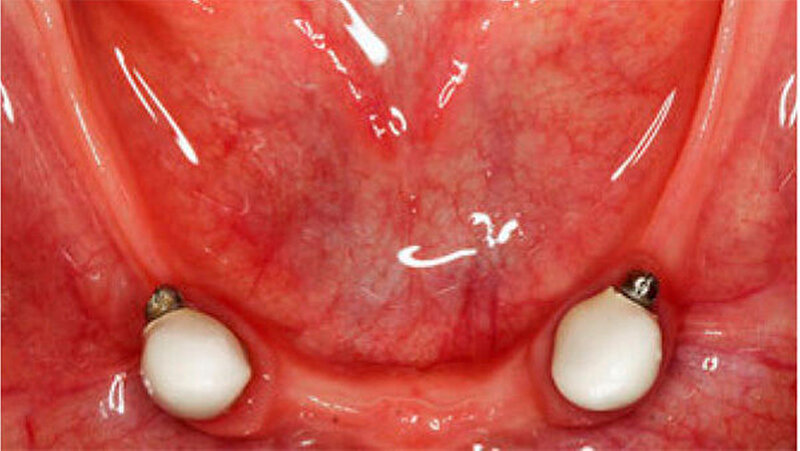

Bei dieser bei Behandlungsbeginn 16-jährigen Patientin waren seit Geburt nur die beiden ersten Molaren im Oberkiefer ausgebildet. Die Folge waren schmale und niedrige Alveolarkämme mit einem flachen Gaumengewölbe (Abb. 16 und 17). Die röntgenologische Abbildung bestätigte das geringe vertikale Knochenangebot. Eine Formanomalie der Zahnwurzeln ließ auf taurodonte Molaren schließen. Beide Molaren wiesen ausgedehnte kariöse Läsionen auf (Abb. 18).

Die Patientin war mit einer knapp neunjährigen Teilprothese im Ober- und einer zweijährigen Totalprothese im Unterkiefer versorgt. Beim Lachen wurden die nicht mehr altersentsprechenden Prothesenzähne mit den deutlichen Randverfärbungen ersichtlich (Abb. 19). Das sagittale Wachstum des zahnlosen Unterkiefers führte in den letzten zwei Jahren aufgrund der verstärkten Kontakte im Frontzahnbereich zu einer beidseitigen Nonokklusion im Seitenzahnbereich (Abb. 20). Eine rasche Verbesserung der Ästhetik als auch der Funktion war unbedingt angezeigt, um das Selbstbewusstsein dieses puberalen Mädchens zu stärken.

Aufgrund des anatomisch sehr ungünstigen Prothesenlagers war der Erhalt der Restbezahnung im Oberkiefer anzustreben. Nach Kariesexkavation und Wurzelkanalbehandlung konnten beide Zähne mit einer Wurzelstiftkappe versorgt und die alten Prothesen entsprechend umgebaut werden. Im Anschluss an die Meisterabformungen und an die Ausrichtung der Wachswälle wurden die Modelle schädelbezogen einartikuliert, und die Prothesenzähne nach ästhetischen und funktionellen Richtlinien aufgestellt. Eine bilateral balancierte Okklusionsbeziehung konnte umgesetzt werden. Im Oberkiefer wurde eine gerüstverstärkte Totalprothese hergestellt, die auf den beiden Wurzelstiftkappen 16 und 26 verankert war. Im Unterkiefer konnte die Patientin mit einer Totalprothese versorgt werden (Abb. 21 bis 23).